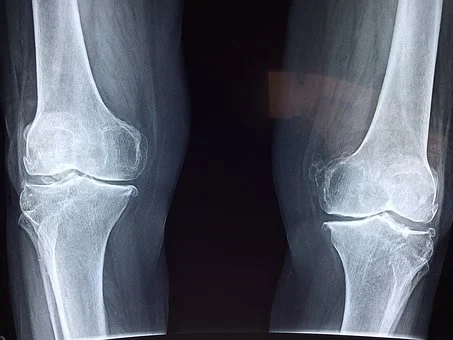

초록입홍합 오일을 가지고 동물 실험으로 관절 손상도를 테스트한 결과

초록입홍합 오일을 복용한 실험군에서 관절 손상도가 현저히 낮아지는 연구 결과를 보였다고 합니다.

국내 7개 대학병원에서 임상시험도 진행했는데요.

초록입홍합 추출 오일을 1개월 투여하자 57%의 관절 기능이 개선되는 결과를 보였다고 합니다.

2개월 이후에는 83%의 개선 효과를 보였다고 하니 초록입홍합이 관절에 미치는 긍정적인 영향은 의심하지 않으셔도 되겠습니다.